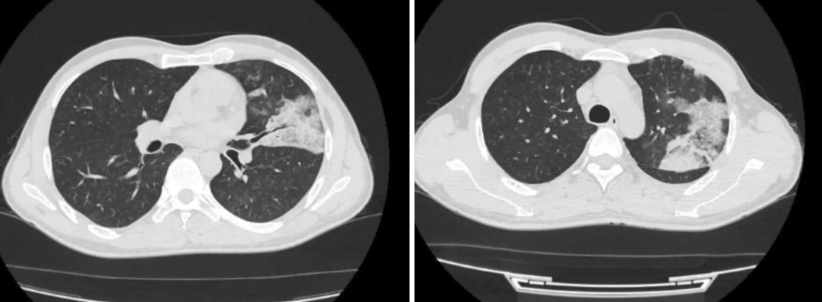

△患者康康(化名)2025年10月的CT影像

患者康康(化名)39岁,西南某省人,2025年10月他因受凉出现咳嗽、咳痰,在当地医院做胸部CT检查提示左肺斑片状渗出影,疑似肺炎。

这个青年男子曾以为自己只是一场“顽固的肺炎”,直到在重庆医科大学附属第一医院呼吸与危重症医学科就诊后,病理报告上“肺腺癌”三个字刺入眼帘。

2025年10月,康康因咳嗽在当地医院被诊断为“肺炎”,抗生素、中药轮番上阵,症状却愈演愈烈。半年后CT显示:左肺病灶疯长,右肺新发多处渗出灶。